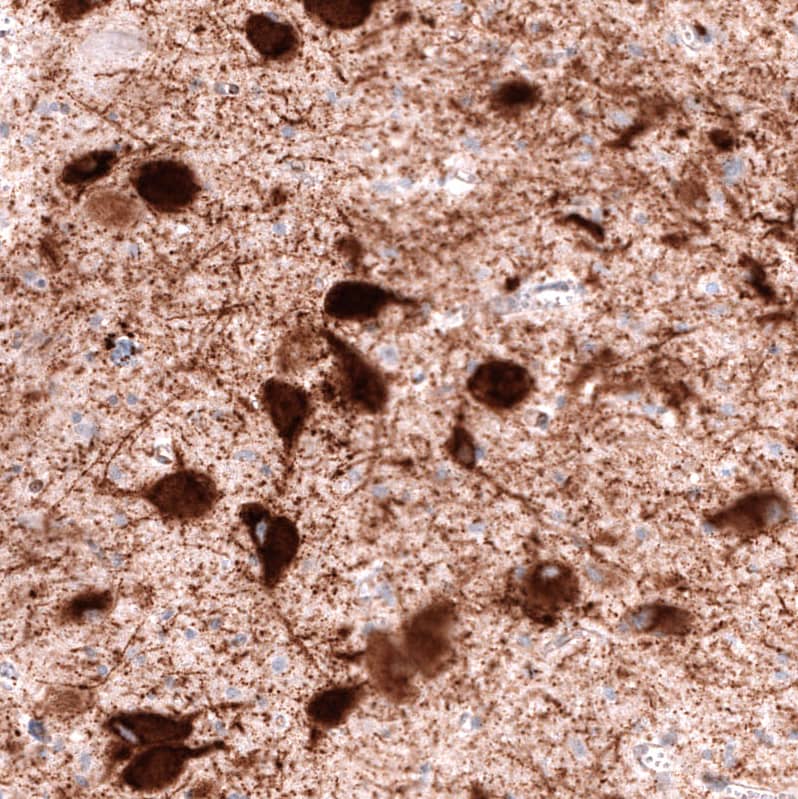

Immunohistochemistry-Paraffin: VMAT2 Antibody [NBP3-44389]

Staining of human dorsal raphe nucleus shows strong cytoplasmic positivity in neurons.Applications for VMAT2 Antibody (CL12531) - Azide and BSA Free